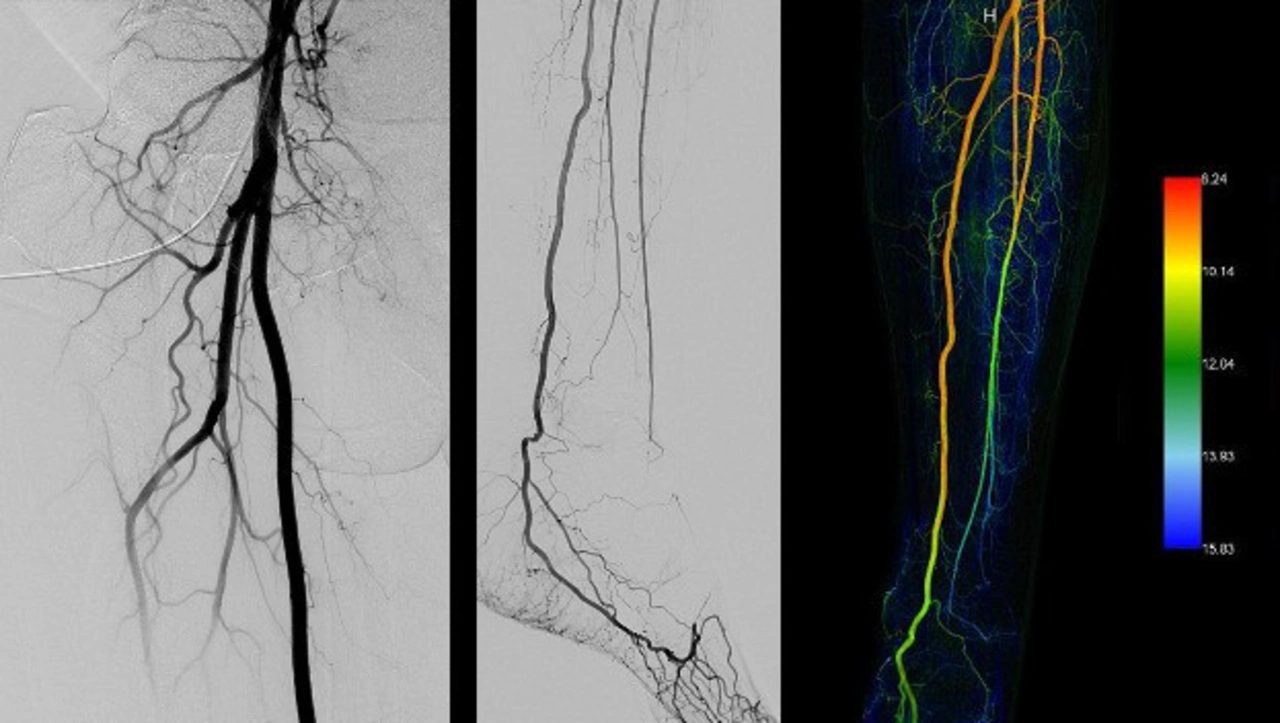

Periphere Arterienerkrankung. Mit freundlicher Genehmigung der Medizinischen Hochschule Hannover

Neue Steuerungen und Antriebe im C-Bogen

Neue Steuerungen und Antriebe im Omni Spin C-Bogen von Artis icono ceiling erlauben

eine schnelle Rotation und exakte Systembewegungen. 3D-Aufnahmen sind in nur

zweieinhalb Sekunden möglich, sodass Bewegungsartefakte reduziert werden können.

Dank der hohen Positionierungsgenaugkeit muss die Aufnahme des Gefäßbaumes für die bildgestützte Katheternavigation nur einmal gemacht werden, was zu Einsparungen bei Kontrastmittel und Dosis führen kann. Werkzeuge zur intelligenten Bildführung

unterstützen zudem in der Anwendung bei anatomischer Navigation und

softwaregestützter Identifizierung von Tumor-zuführenden Gefäßen.

Artis icono ceiling ist seit April dieses Jahres an der Medizinischen Hochschule Hannover im Einsatz. »Das neue System funktioniert sehr präzise und die Bildführung ist exzellent«, sagt Prof. Dr. Bernhard Meyer, Leiter der Interventionellen Radiologie. »Artis icono ceiling hat Embolisationen für uns vereinfacht – darunter auch sehr komplexe Eingriffe. Wir können selektiv, aber gleichzeitig umfassend arbeiten und so den Tumor behandeln, während wir gesundes Gewebe schützen.«